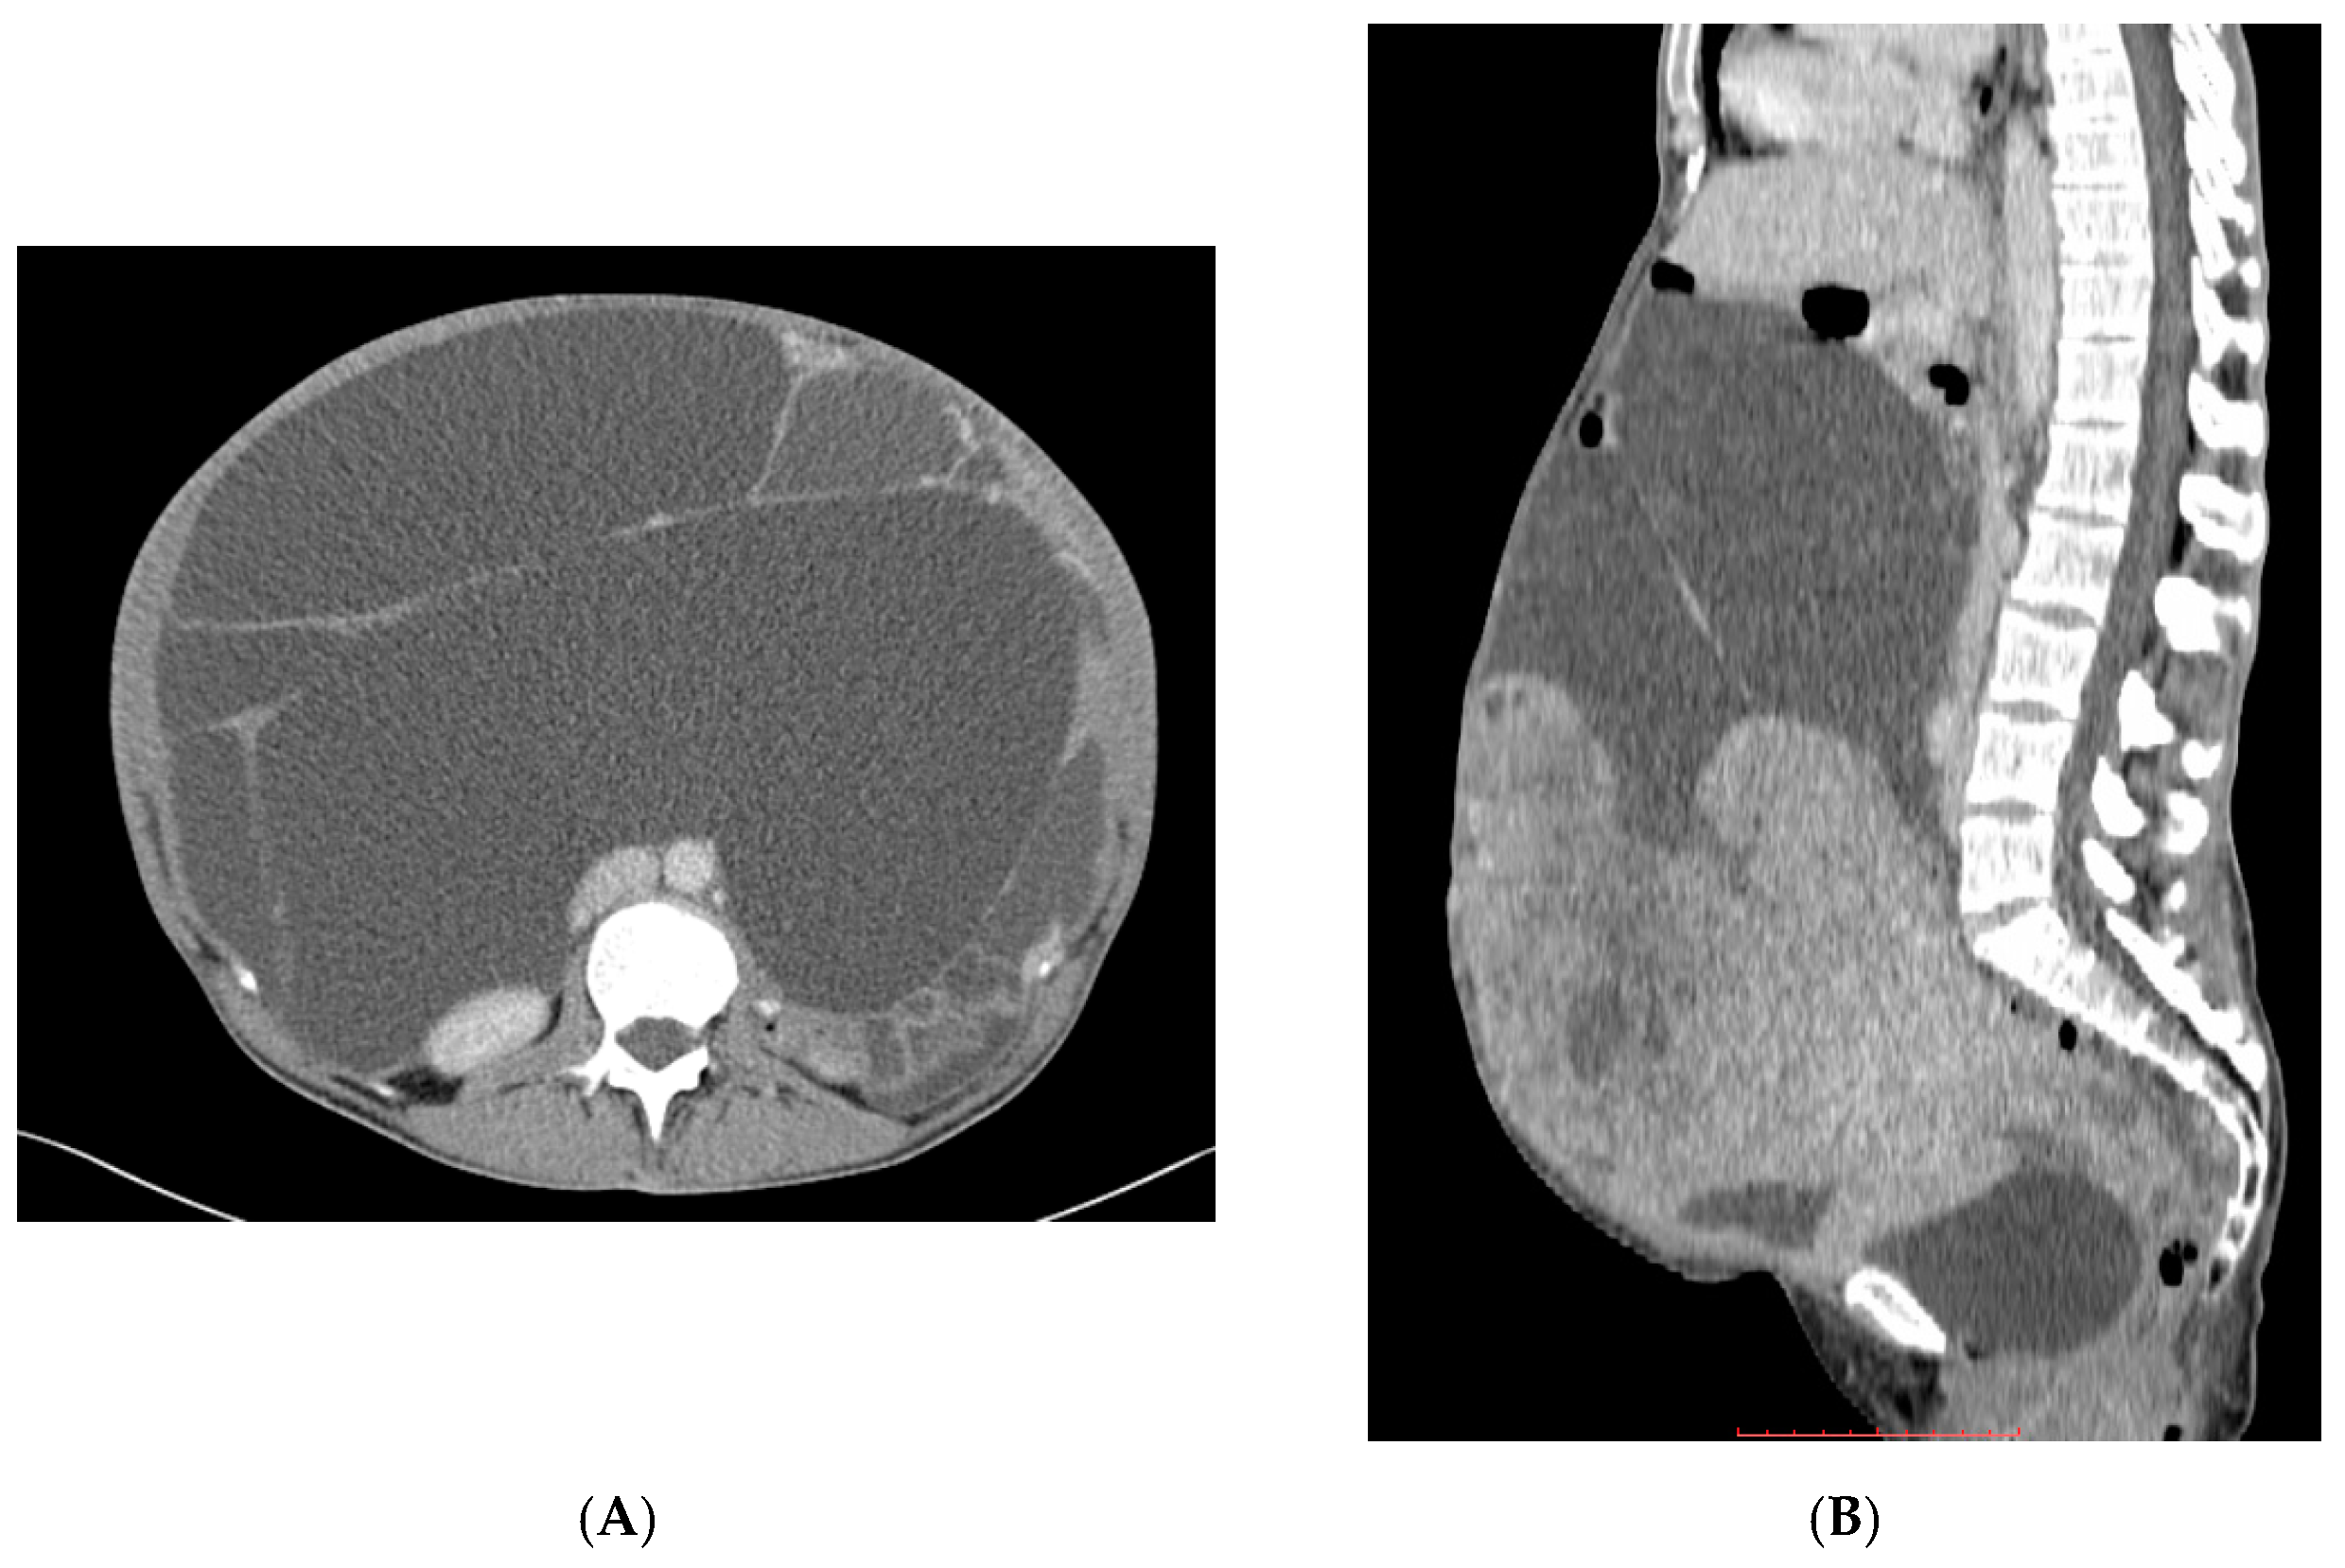

- Tirumani, S.H.; Shinagare, A.B.; Hargreaves, J.; Jagannathan, J.P.; Hornick, J.L.; Wagner, A.J.; Ramaiya, N.H. Imaging features of primary and metastatic malignant perivascular epithelioid cell tumors. AJR Am. J. Roentgenol. 2014, 202, 252–258. [Google Scholar] [CrossRef] [PubMed]

- Bergamo, F.; Maruzzo, M.; Basso, U.; Montesco, M.C.; Zagonel, V.; Gringeri, E.; Cillo, U. Neoadjuvant sirolimus for a large hepatic perivascular epithelioid cell tumor (PEComa). World J. Surg. Oncol. 2014, 12, 46. [Google Scholar] [CrossRef] [PubMed] [Green Version]